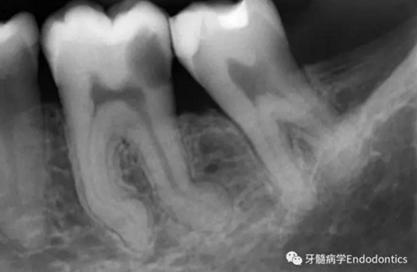

圖2.疏通根管冠方2/3后,使用次氯酸鈉溶液沖洗根管,且可以使用手用器械、GG鉆(刷洗動作)、旋轉鎳鈦成形銼預敞根管。當冠方2/3進行了合適的預備且充滿沖洗液后,接著進行根尖1/3的探查以收集信息。使用小的手用銼(8號或10號K銼)疏通根管的剩余部分,確認建立了流暢的、無阻礙的、平滑的到達根尖止點的引導通道。

圖3.存在細小狹長、可能多維的復雜根管解剖時,使用10號K銼不可能立即疏通根管到達根尖止點。隨后醫(yī)生應嘗試使用更小的銼探查以達到根尖。但是,通常不需要使用6號和8號K銼對到達根尖的引導通道進行擴大,除非是特別困難的病例。